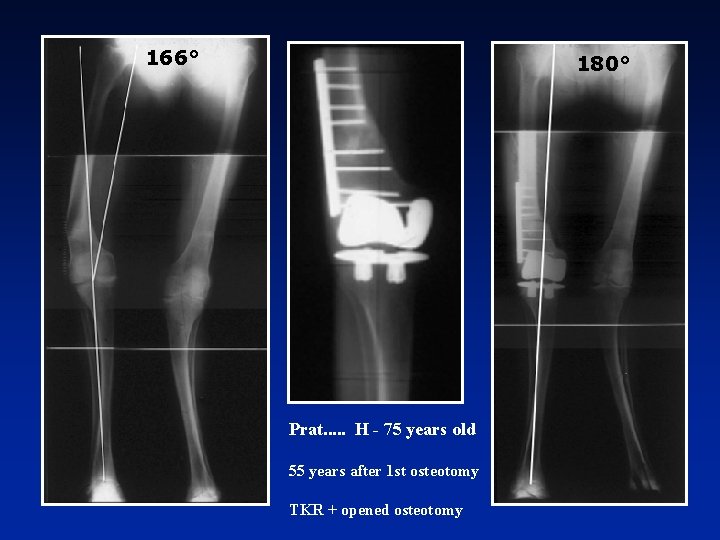

166° 180° Prat. . . H - 75 years old 55 years after 1 st osteotomy TKR + opened osteotomy